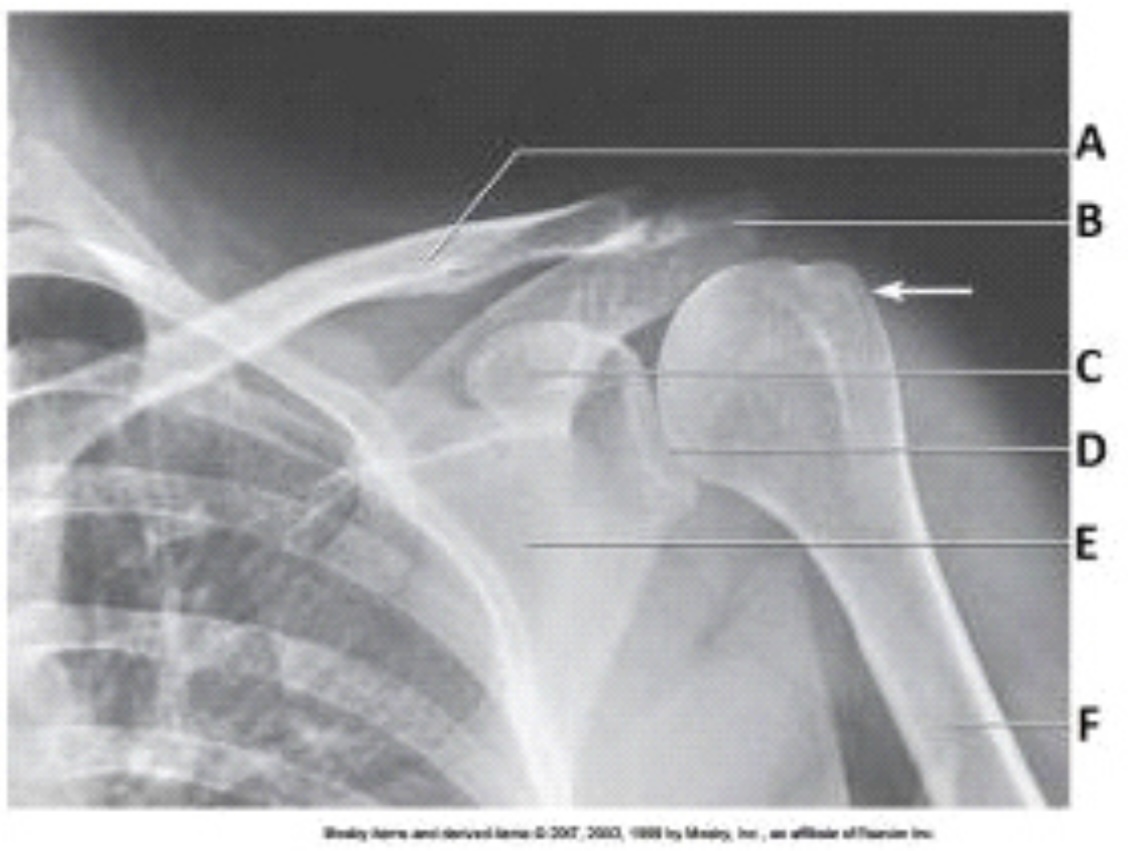

What projection, position, and anatomy of interest in the image below is demonstrated?

AP projection of the shoulder in internal rotation

The anatomy labeled in the image below by the arrowhead is the:

lesser tubercle.